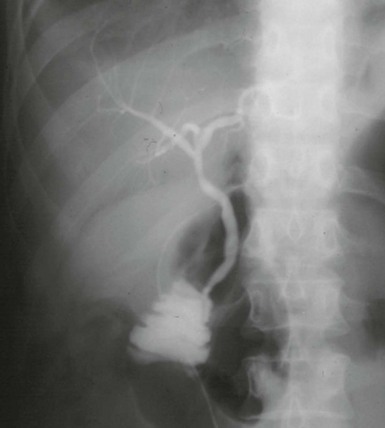

Investigating the biliary duct system: See Figure 20.5.

Fig. 20.5 Investigation of the biliary duct system

(b) Endoscopic retrograde cholangiogram in a woman of 77 who presented with mild epigastric pain and obstructive jaundice. The film shows multiple large stones in the common bile duct, represented by filling defects. The common bile duct is moderately dilated, but the intrahepatic ducts IHD are not. The fundus and neck of the gall bladder GB are shown, but the body is empty of contrast (dotted lines). There is a stone S near the neck of the gall bladder